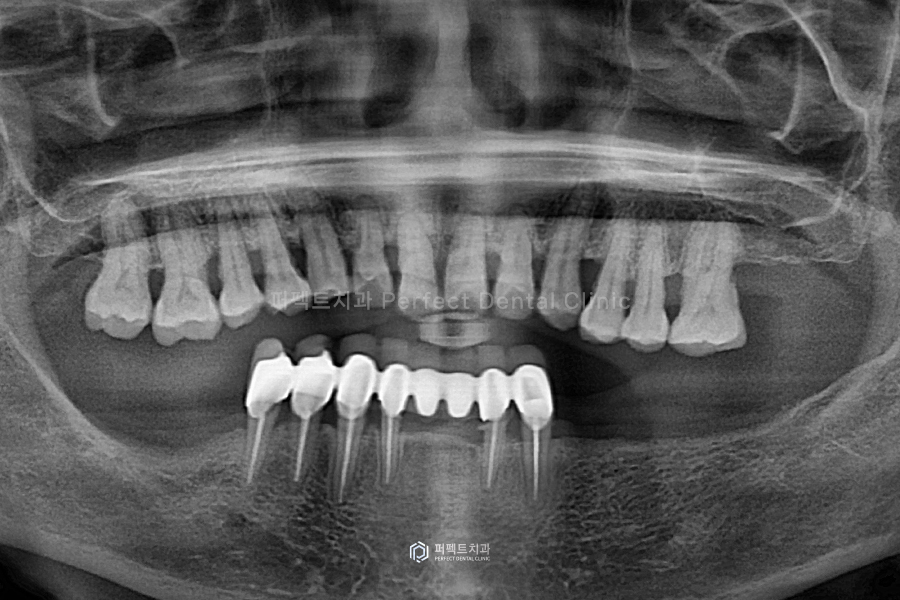

처음 병원에 내원 하셨을 당시 파노라마 엑스레이 사진입니다. 아랫니는 앞니 쪽에만 치아가 있고, 윗니는 왼쪽 어금니 하나를 제외한 전체 치아가 남아있는 상태였습니다.

어금니가 없는 아랫니는 부분틀니를 사용하시고 있는 상황이었는데요. 환자분께서는 아랫니의 경우 부분틀니도 불편하고, 남아있는 아랫니 앞니 부분도 다 흔들린다고 말씀을 하셨고, 윗니 또한 전체적으로 치아가 흔들리고 아프다고 하셨습니다.

한 번 보시면 '교합평면'이 무너져 있는 상황입니다. 치아가 반듯하게 균형이 맞아야 하는데, 아래 어금니가 없어 위 어금니가 아래로 쏟아져 내려와 교합이 무너지게 된 것인데요. 이러한 상태에서 틀니를 제작해서 사용하다보니 균형도 안맞고, 잘못된 힘을 계속 받게 된 것 입니다.